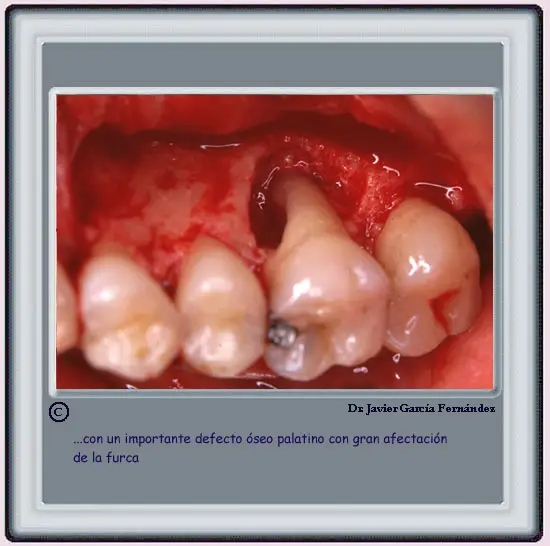

image267